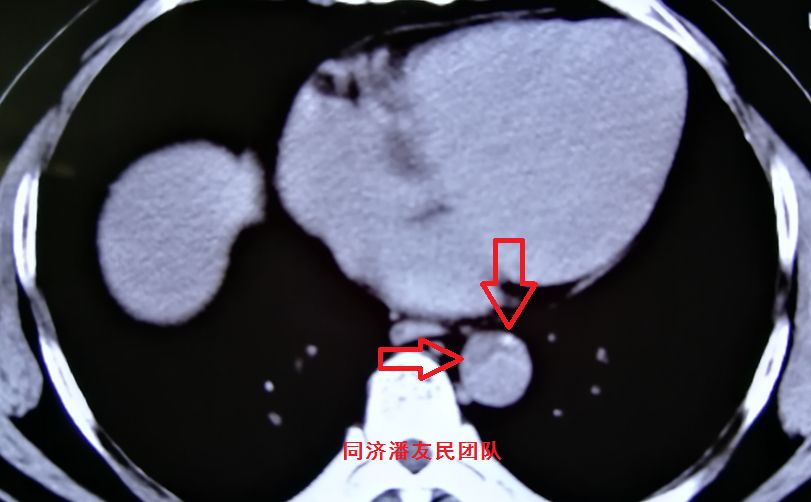

结果在上级医院复查胸腹主动脉CTA,在平扫CT提示主动脉夹层的对应层面,证实了主动脉夹层(图3~6)。同时发现升主动脉及主动脉弓均有夹层撕裂 (图7~8) 。 因此,正确诊断应该是 A型 (1型) 主动脉夹层。

图3:平扫CT提示胸降主动脉血管内膜征及血管周围钙化点(箭头所示),此血管周围钙化点并非主动脉夹层征象

图4:CTA显示图3相应层面,与平扫CT对应的血管内膜征及血管周围钙化点(红箭头所示)